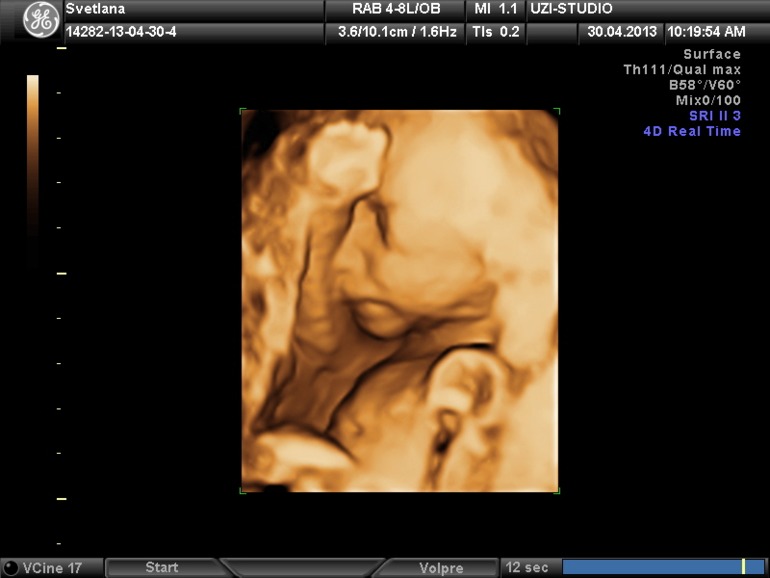

Светлана в Благополучная беременность 12 лет В субботу 3 УЗИ.хочу опять посмотреть на эту мордашку ;) УЗИ, КТГ, доплер Сын в 21 неделю ;)) Посмотрите еще 20 записей на эту тему Отменить Ответить Татьяна Показался, молодец) А я ходила на 4D узи дважды и дважды отворачивался((( Так и не удалось лицо посмотреть( 17.07.2013 Ответить Светлана кое как уловили ))весь вошкалсявсе смазывалось ))) 17.07.2013 Ответить Делала Узи у Шульца, срок 16-17 недель.. Может ли плацента опуститься? Чаты Беременных Выберите чат: Январята-2026 Февралята-2026 Мартята-2026 Апрелята-2026 Майчата-2026 Июнята-2026 Июлята-2026 Августята-2026